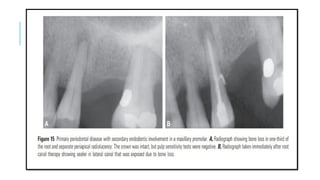

PRIMARY PERIODONTAL DISEASE WITH

SECONDARY ENDODONTIC INVOLVEMENT

 A periodontal pocket may continue and progress until the apical tissues are

involved. In this case, the pulp may become infected due to irritants entering via

lateral canals or the apical foramen and subsequently become necrotic.

 In single-rooted teeth, the prognosis is usually poor. In molar teeth, the

prognosis may be better because not all the roots may suffer the same loss of

supporting tissues.

 In some of these cases, root resection can be considered as a treatment alternative